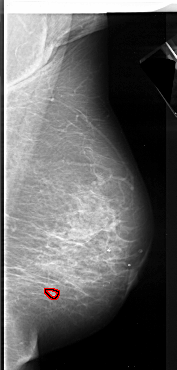

FILE: A_1085_1.RIGHT_MLO.OVERLAY

TOTAL_ABNORMALITIES 1

ABNORMALITY 1

LESION_TYPE CALCIFICATION TYPE ROUND_AND_REGULAR DISTRIBUTION CLUSTERED

ASSESSMENT 4

SUBTLETY 4

PATHOLOGY MALIGNANT

TOTAL_OUTLINES 1

BOUNDARY

FILE: A_1085_1.RIGHT_CC.OVERLAY